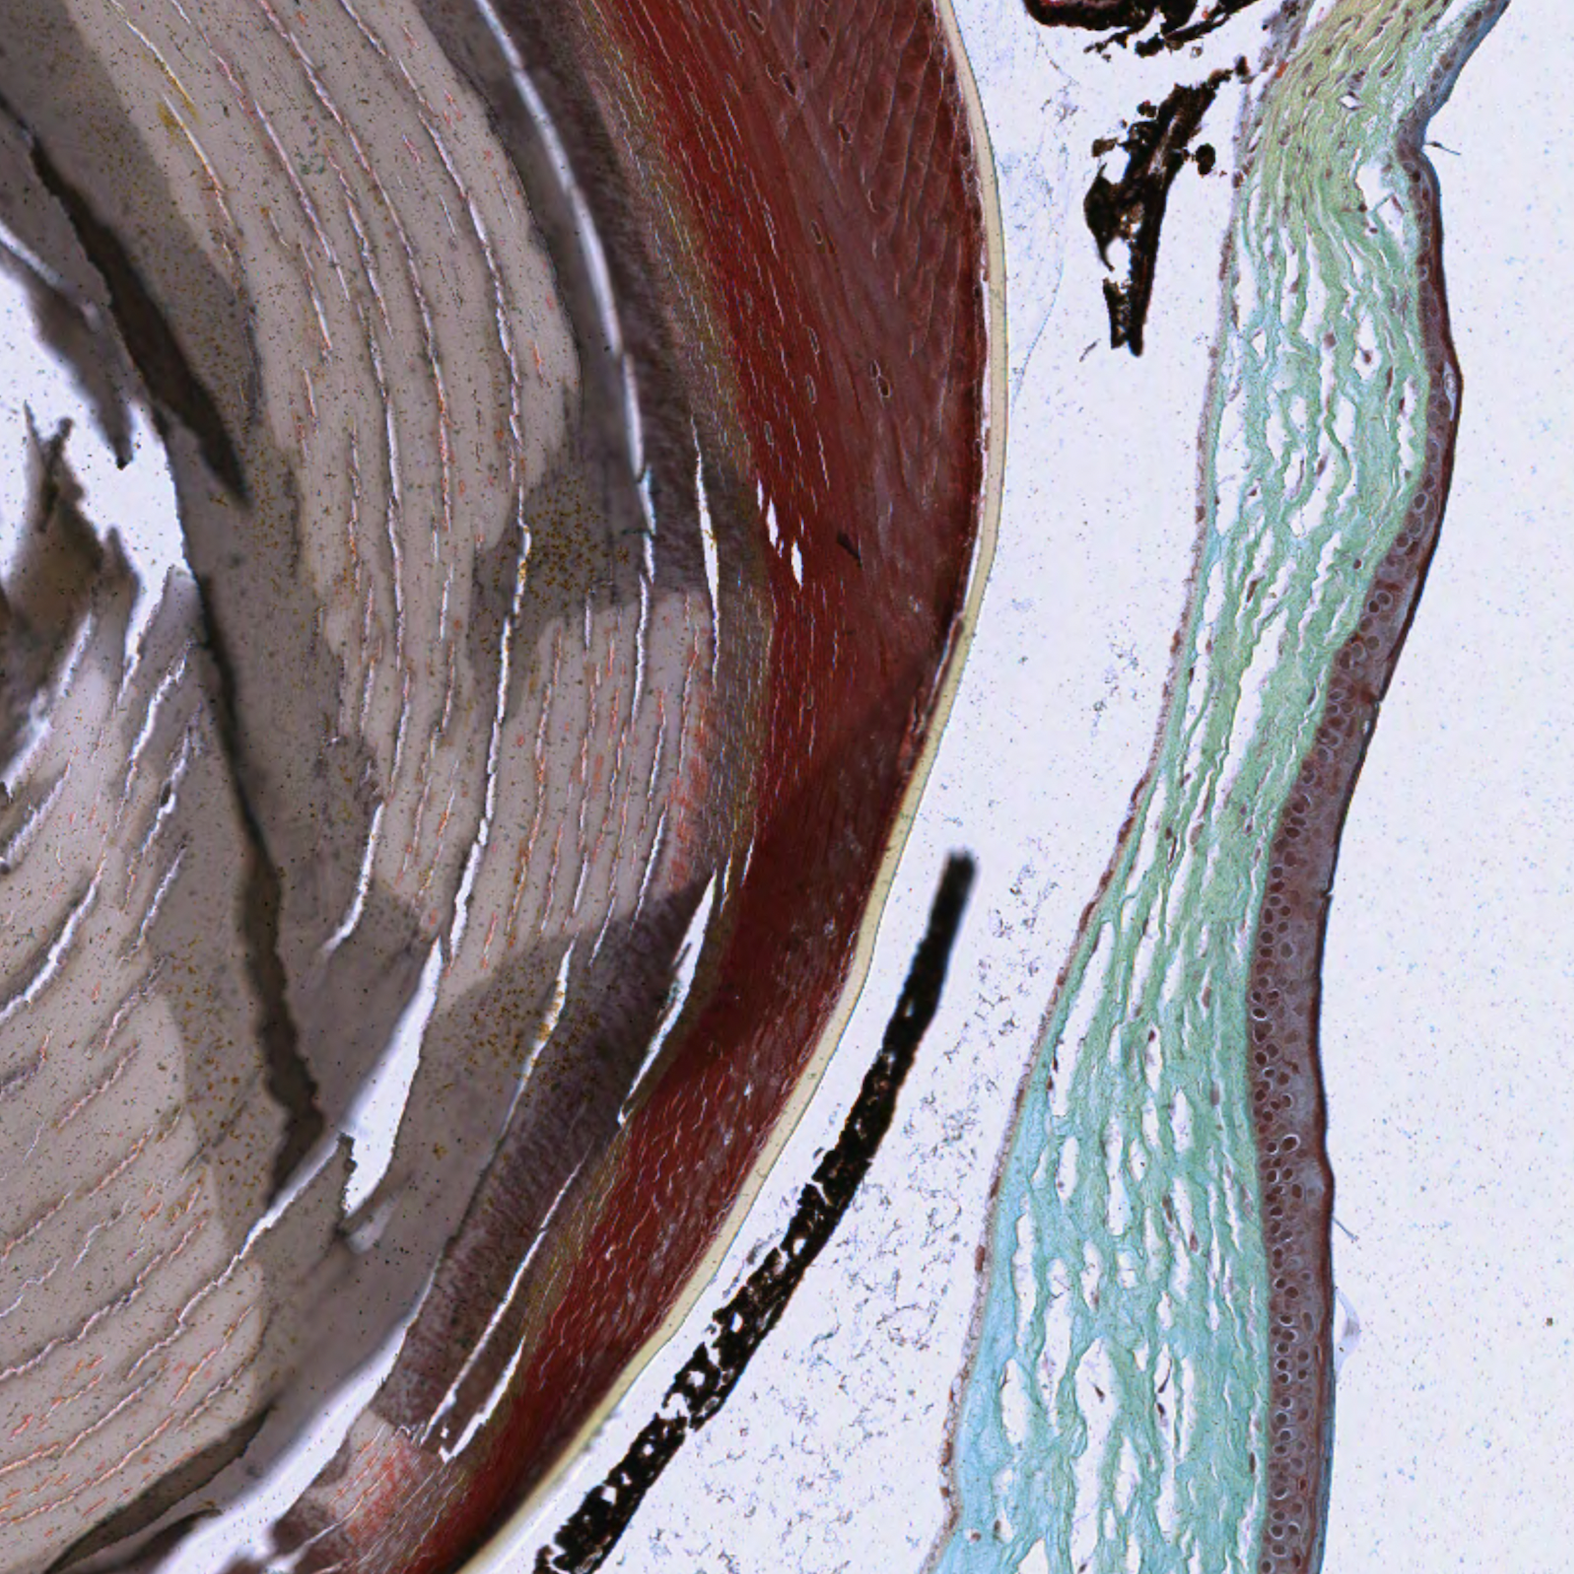

Cornea

| Eye_Cornea_H&E_01.svs Eye_Cornea_H&E_01.tif |

Eye_Cornea_Pen_01.svs Eye_Cornea_01.tif |

The corneal layers are better visualized using the pentachrome stain kit. The pentachrome stain kit also finely stains the rod cells and allows for easy differentiation of the microstructures of the retina and cornea. The pentachrome stain kit is therefore a finer stain for the fibrillar structures. However, the nuclear staining is not as strong and the inflammatory cells might be less precisely identified.